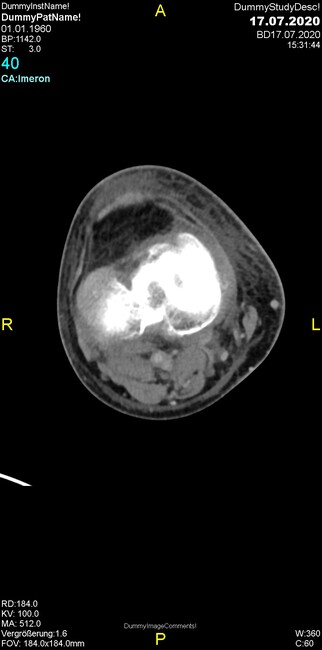

Um welche Modalitäten handelt es sich?

- Röntgen p.a. und lateral, CT coronar Knochenfenster, CT axial Weichgewebsfenster

- Röntgen p.a. und oblique, CT coronar Knochenfenster, CT axial Weichgewebsfenster

- Röntgen p.a. und lateral, CT sagittal Weichgewebsfenster, CT coronar Knochenfenster

- Röntgen p.a. und oblique, CT sagittal Knochenfenster, CT coronar Weichgewebsfenster

- Röntgen p.a. und lateral, CT coronar Weichgewebsfenster, MR axial

Was fällt in der Projektionsradiographie auf?

- Verdichtung im Recessus suprapatellaris

- Aufhellungslinie in Projektion auf die Femurkondylen

- Erhöhter tibialer Slope

- Hypertransparenz tibial

- Subluxationsstellung im Kniegelenk

Was trifft auf den Befund zu?

- Der Befund beschränkt sich auf den Knochen.

- Es besteht hochakuter Handlungsbedarf.

- Der Befund ist tendenziell benigne.

- Der Befund ist tendenziell maligne.

- Der Befund weist einen Zusammenhang zum Patientenalter auf.

Was fällt in der CT im Knochenfenster auf?

- Mediale Gelenkspaltverschmälerung

- Dezente Erosion der fibulären Kortikalis

- Frakturspalt der lateralen Tibiametaphyse

- Weichgewebskalzifikationen lateral angrenzend an den Gelenkspalt

- Osteolyse der Tibiametaphyse unter Beteiligung der Kortikalis

Was kommt differentialdiagnostisch in Frage?

- Kompartmentsyndrom

- Osteomyelitis mit Weichgewebsanteil

- Metastase mit pathologischer Fraktur

- Rheumatoide Athritis

- Posttraumatische Verletzung